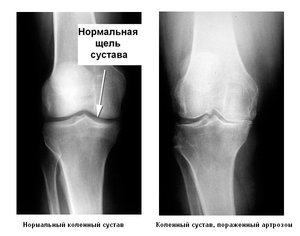

- рентген пораженного сустава показывает, что непосредственно полость сужена и на костях образовались остеофиты;

- на рентгене видны значительные изменения околосуставных тканей и суставной полости;

- на рентгене видно локальное разрушение менисков, связок, признаки склероза, истирание хряща, срастание костей в суставной полости;